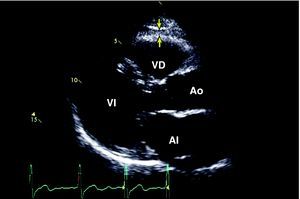

Efecto paracrino de la grasa subepicárdicaEl tejido adiposo subepicárdico es una forma particular de tejido adiposo visceral depositado alrededor del corazón, primordialmente alrededor de las arterias coronarias subepicárdicas (Figura 2). Aunque a simple vista esa descripción podría ser sólo una curiosidad anatómica, hay evidencia de la importancia fisiológica y metabólica de dicho tejido adiposo, especialmente en la asociación con el riesgo cardiovascular y la patogenia de la aterosclerosis coronaria10,38. Estudios en cadáveres han demostrado que el peso de la grasa subepicárdica se relaciona con el peso total del corazón, y la placa aterosclerótica de las coronarias tiende a ser más prominente en el lado de las arterias en contacto con los depósitos de grasa. Otros estudios han demostrado que la grasa subepicárdica suministra ácidos grasos libres para la producción de energía y la síntesis de citocinas. Estudios en animales indican que la tasa de síntesis de ácidos grasos es mayor en la grasa subepicárdica que en otros lugares del cuerpo39,40. Además, se ha demostrado que la grasa subepicárdica de pacientes con enfermedad coronaria grave es una fuente de producción de diversos mediadores de inflamación y tiene una marcada respuesta a la inflamación, independientemente del IMC o la diabetes41. Nuestro grupo ya había demostrado que el grosor del septo interauricular, que se relaciona con la cantidad de grasa subépicardica, se correlaciona con la presencia y la gravedad angiográfica de la enfermedad coronaria42. La medida de la grasa subépicardica en el ventrículo derecho o la cantidad alrededor del corazón también se relacionan con la circunferencia abdominal, la presión arterial diastólica, la masa del ventrículo izquierdo, la concentración elevada de insulina, la captación de glucosa y la gravedad de la enfermedad coronaria evaluada por angiografía coronaria43,44,45,46,47.

Figura 2. Delineación de la grasa subepicárdica por ecocardiografía bidimensional en el plano paraesternal de eje largo 38 . Las flechas identifican el espacio ecoico entre el subepicardio y el pericardio. AI: aurícula izquierda; Ao: aorta; VD: ventrículo derecho; VI: ventrículo izquierdo.

De Vos et al48 examinaron la localización particular de la grasa subepicárdica en mujeres posmenopáusicas con tomografía computarizada, y mostraron una relación entre la grasa subepicárdica que rodea directamente las arterias coronarias y diversos factores de riesgo vascular y la falta de relación entre grasa subepicárdica e IMC. Los autores también encontraron que la grasa pericoronaria está relacionada con la calcificación de las coronarias.

Es muy posible que los mediadores inflamatorios fuera de la arteria coronaria, como la inflamación subpericárdica y adventicia, contribuyan a las lesiones ateroscleróticas. La cercana relación entre la grasa subepicárdica y las arterias coronarias adyacentes permite la interacción paracrina entre dichas estructuras38.

A pesar de que diversos estudios indican una potencial función de la grasa subepicárdica en el desarrollo de la enfermedad coronaria, el mecanismo exacto requiere más estudios.